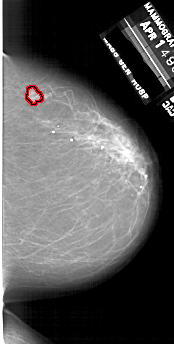

FILE: A_1747_1.RIGHT_MLO.OVERLAY

TOTAL_ABNORMALITIES 1

ABNORMALITY 1

LESION_TYPE MASS SHAPE LOBULATED MARGINS ILL_DEFINED

ASSESSMENT 4

SUBTLETY 3

PATHOLOGY BENIGN

TOTAL_OUTLINES 1

BOUNDARY